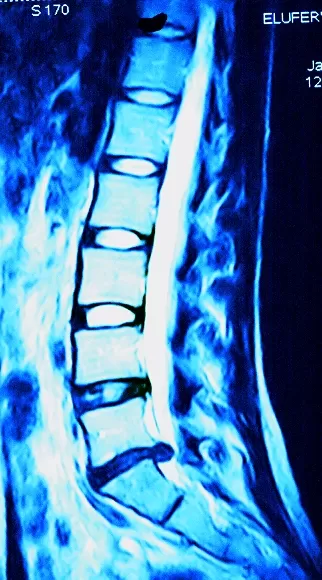

Грыжа межпозвоночного диска L4–L5 (17 мм), Грыжа межпозвоночного диска L5–S1 (15 мм), Спинальный стеноз

Пациентка Е-а, 31 год, на протяжении нескольких последних лет отмечает боли в пояснице, усиливающиеся при ходьбе и физической нагрузке. Боли отдают в обе ноги. Нарастающая слабость в обеих ногах. Пациентке назначено оперативное вмешательство с заменой двух межпозвонковых дисков и наложением протеза типа «легаси».

Позвоночник: При пальпации остистых отростков выраженная болезненность в поясничном отделе позвоночника L3–L5 Болезненность при пальпаторном исследовании поясничного отдела позвоночника в паравертебральной области и по ходу обоих седалищных нервов. Пальпация точек выхода седалищного нерва болезненна с обеих сторон. При вызывании феномена межпозвонкового отверстия — иррадиация боли из грыжевой точки. Двусторонняя параплегия.

На МРТ пояснично-крестцового отдела позвоночника отмечается:На серии томограмм (Т1 и Т2–ВИ, сагитальная, аксиальная, фронтальная проекции) высота межпозвонкового диска L4–L5 снижена до 3 мм, высота межпозвонкового диска L5–S1 неравномерно снижена до 2 мм. Выраженная дегидратация межпозвонковых дисков L4–L5 и L5–S1. На уровне L4–L5 определяется задняя медиальная протрузия 17 мм, сдавливающая дуральный мешок в передних отделах. На уровне L5–S1 определяется нисходящая медианно-парамедианная грыжа с латерализацией влево высотой до 15 мм, сдавливающая дуральный мешок в передних отделах, переднюю и заднюю ветви спинального нерва и ветви конского хвоста слева. Задняя продольная связка на уровне L4–L5 и L5–S1 смещена кзади, уплотнена.

На повторной МРТ: Межпозвонковый диск L4–L5 БЕЗ ИЗМЕНЕНИЙ. Снижена высота и интенсивность МР-сигнала на Т2 ВИ межпозвоночного диска L5–S1. Фрагмент межпозвонкового диска L5–S1 пролабирует в просвет позвоночного канала на 2 мм. Дуральный мешок не деформирован, паравертебральные мягкие ткани без изменений.

Заключение — МР-признаки дистрофических изменений и остеохондроза поясничного отдела позвоночника в сегменте L5–S1.